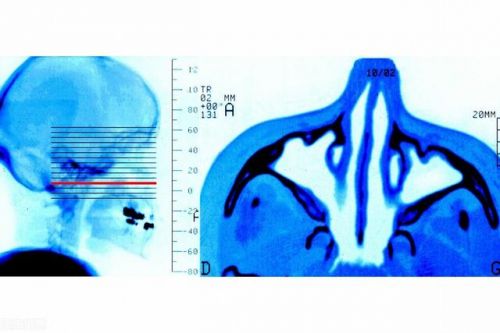

鼻科疾病的代表当属鼻炎。鼻炎,也就是鼻黏膜的炎性疾病,鼻炎的分类很多,但是咱们通常所指的鼻炎通常指的就是慢性鼻炎,慢性鼻炎它是鼻粘膜的慢性疾病。

慢性鼻炎一般症状有鼻塞、流鼻涕,有时候头部昏沉感。得不到及时有效的治疗,炎症上下延伸,会影响到耳鼻喉其他的部位,甚至发生全身的病变。如骨髓炎、眶内蜂窝组织炎、脑膜炎、脑脓肿、眼病,中心性视网膜炎,致生命危险。